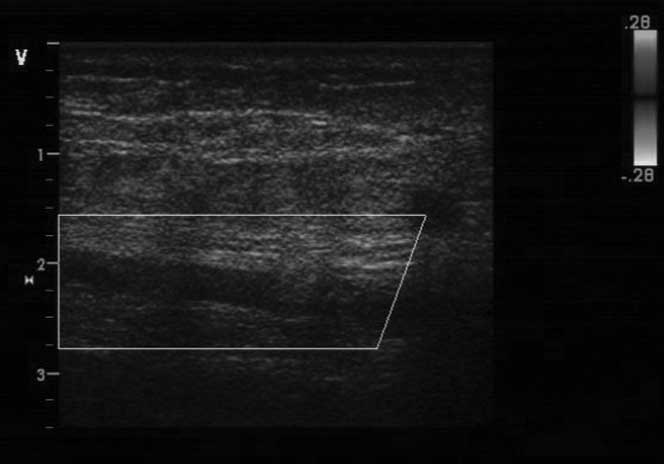

On days 20, 27 and 28 of chemotherapy, the thrombus in the axillary

and brachial veins disappeared in a 50-year-old female with

cervical cancer, a 31-year-old female with brain metastases and a

47-year-old male with lung cancer, respectively (Fig. 2). The cost of the PNS treatment was